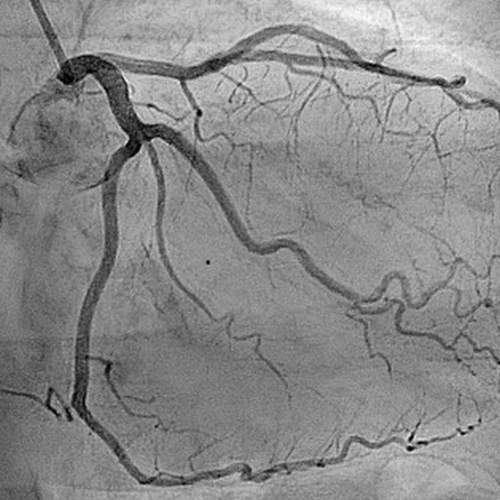

We have a huge number of cases with different modalities and regions

By Modality

By Region